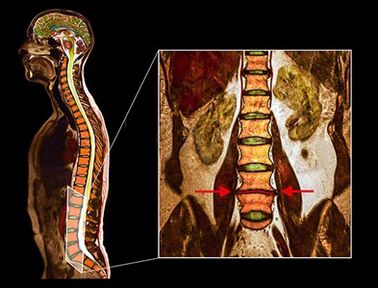

- I metodi diagnostici di cui sopra sono generalmente sufficienti per la diagnosi di osteocondrosi, ma una diagnosi accurata richiede l'uso di metodi di visualizzazione.

- Ct

- Radiografia

- MSCT

- Pat

- MRI - Questo metodo diagnostico consente di chiarire il grado di degenerazione, la presenza di fratture, le ernie dei dischi di stenosi. Spesso è necessario uno studio di risonanza magnetica in preparazione al trattamento chirurgico al fine di determinare accuratamente la posizione del disco degenerato e pianificare l'operazione.

Gli studi hanno dimostrato che i risultati della risonanza magnetica con dischi moderati o significativi si trovano durante la scansione dei pazienti, sia con dolore grave che minimo o mancanza di dolore. Inoltre, molte condizioni dolorose potrebbero non apparire su una risonanza magnetica. Per questo motivo, la diagnosi non può essere effettuata esclusivamente sulla base dei risultati della visualizzazione e la verifica della diagnosi è possibile solo sulla base della totalità di tutti i metodi di esame clinico e strumentale.